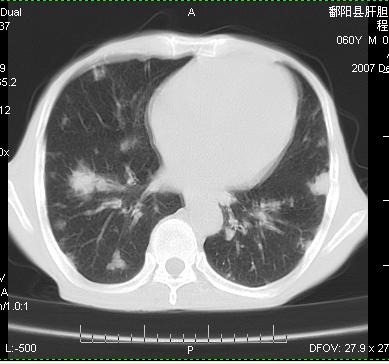

两肺示有散在大小不等类园形边缘不整密增高影.

考虑多发性转移瘤.请各位老师指导.

双侧胸壁见多发结节软组织密度灶,两肺内见广泛结节状、面团样影,两肺及胸膜多发性转移瘤。支持

根据:病变确实是多发,但大部分边缘不光滑,欠规整,密度不均匀。也就是说“大部分病灶不是典型转移瘤的表现”。转移瘤可以不典型,但如此大部分不典型,却是很少见的。结合发烧病史,考虑肺多发小脓肿或其他炎性病变,如霉菌等感染!建议痰培养,抗炎治疗后复查!

从病人年龄及肺内表现首先考虑转移瘤,但病人以咳嗽发热胸痛为首发症状还要考虑血行播散型肺脓肿及白血病非内表现等,结合实验室检查有鉴别意义。